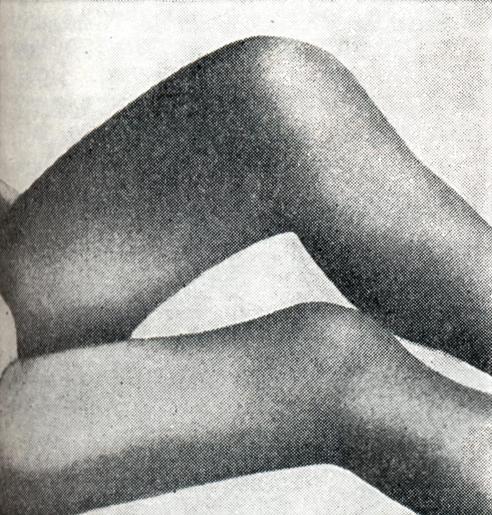

Наиболее характерен метастатический гонит (моноартрит с острым и подострым течением). Морфологически острый гонит может быть серозным или гнойным, подострый — серозно-фибринозным. При всех формах отмечаются мучительные боли, высокая температура, тяжелое общее состояние больного. Развитие патологических изменений в суставе резко выражено: быстро развивается деформация, сгибательные контрактуры (рис. 14), мышечная атрофия. Показатели лабораторных исследований говорят об активности воспалительного процесса. В пунктате можно обнаружить гонококки. При неправильном или запоздалом лечении быстро развивается выраженная деструкция суставных элементов и анкилоз.

Рис. 14. | ||